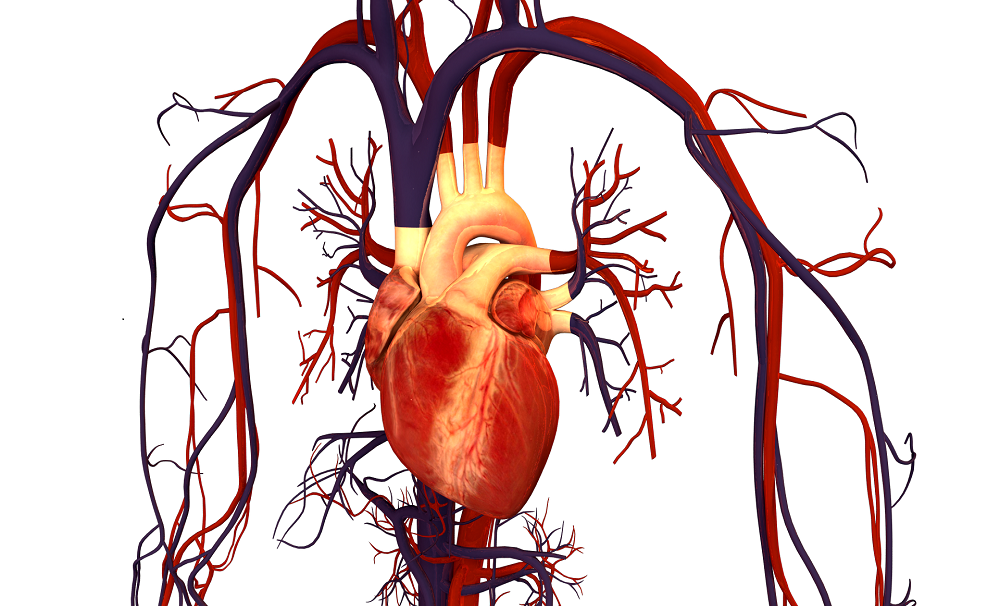

Potato is very much good For Your Heart

I think most of the people don’t know the health benefits of Potato. Potato is very much good for your heart, in potato there is an abundant source of Vitamin B6, so it converts the potentially homocysteine into another harmless substance. In this way potato lowers the risk of heart diseases and protects your heart.

Today modern world has facing Blood Pressure (BP) because of anxiety and work pressure. So, in order to regulate or control the blood pressure, you should eat steamed potatoes twice in a week, fibers present in potato will decrease the cholesterol and improves the functioning of insulin in the body. Furthermore, a compound called kukoamine has been newly reported in potatoes that help in lowering the blood pressure. So don’t forget to eat Potato’s.